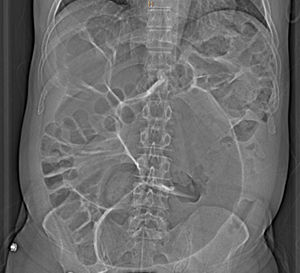

Lab work demonstrated lymphopenia of 11.3% (normal values [NV] 20%–50%) and PCR of 18.6 (NV 0.03–0.05). Chest and abdominal radiographs showed large distention of the colonic loops (Fig. 1) and a slight increase in bibasilar condensation but no infiltrates with compression due to dilated loops of the upper hemithorax. Finally, a computed tomography (CT) scan of the abdomen was requested with expansion to the lung bases (Fig. 2A and B). Emergency CT scan ruled out abdominal disease requiring urgent surgery and revealed notable distension of the dolichosigma with air content; ground glass infiltrates were observed in the left lower pulmonary lobe, which, given the current epidemiological situation, is compatible with COVID infection. Finally, a SARS-CoV-2 PCR was requested, which came back positive.